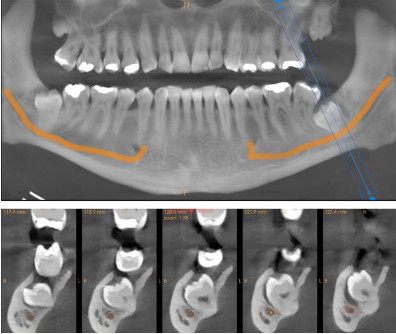

A CBCT scan was acquired using the Carestream CS 8200 to determine the exact 3D relationship between the impacted roots and the IAN canals. The difference between the panoramic view and the CBCT was immediate and clinically decisive.

Cross-sectional views of both sides showed the precise spatial relationship that the panoramic could only hint at. On the right side (LR8), the CBCT confirmed direct contact between the root and the nerve canal. On the left (LL8), the tooth was in close proximity but not in direct contact — a distinction that significantly affects the surgical approach and the informed consent conversation.

Reconstructed panoramic and cross-sections of tooth 48 showing root contact with the mandibular nerve canal Reconstructed panoramic and cross-sections of tooth 38 showing proximity to the mandibular nerve canal

Fig. 2 & 3 Left: cross-sectional views of LR8 (48) confirming direct root contact with the IAN canal. Right: cross-sections of LL8 (38) showing close proximity but no direct contact. This distinction — impossible to make on the panoramic alone — directly affects the surgical risk profile and the consent discussion.